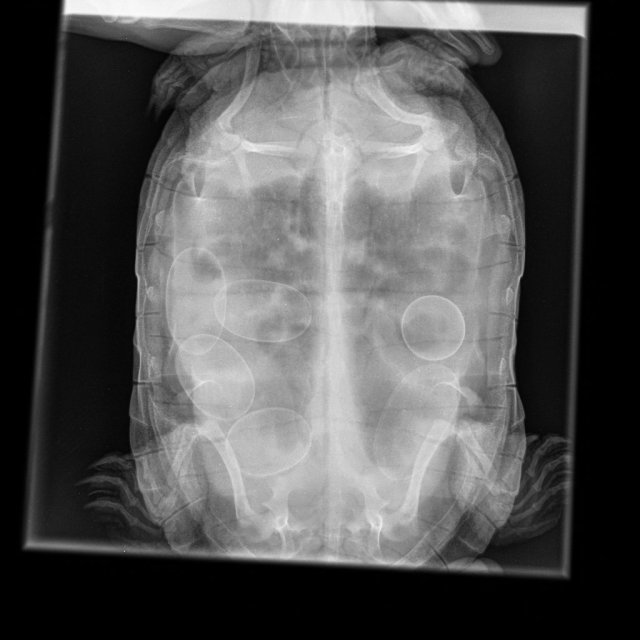

Консультанты moth Ваше имя: Мария Локация: Москва Опубликовано: 27 апреля 2024 Консультанты Опубликовано: 27 апреля 2024 @Ksn.bessonova а у Вас есть снимок на руках? в какой проекции делали? вот на этой картинке под каким номером?

Ksn.bessonova Ваше имя: Анна Локация: Россия, Кем.обл. Новокузнецк Опубликовано: 27 апреля 2024 Автор Опубликовано: 27 апреля 2024 @moth снимок есть, четкий, под номером 1 , завтра смогу выложить. Сегодня поставили марбобел , лапка болит от укола и сама как тряпочка , в аквариуме оставлять не стала, проверила тяжело ей держаться там

Консультанты moth Ваше имя: Мария Локация: Москва Опубликовано: 27 апреля 2024 Консультанты Опубликовано: 27 апреля 2024 @Ksn.bessonova в проекции 1 не видно лёгких, вообще никак. Они скрыты внутренними органами. Лёгкие видно только в проекции 2 и 3. Поэтому я боюсь, что Вы нашли ещё одного плохого специалиста. Марбобел очень тяжело переносится - с рвотой, онемением лапы, параличом и даже смертью черепахи. Без прям необходимости его колоть это издевательство над черепахой. Приложите снимок какой есть и лучше сделать дополнительные проекции, чтобы посмотреть лёгкие